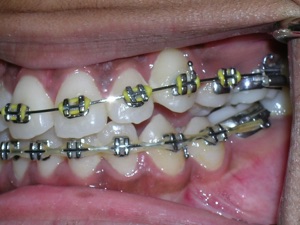

Here again we used a “Nance” holding arch. Look at some photos while the braces are on.